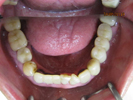

50代女性

![]() |

治療前 |

||

治療中。仮歯。 左上の奥にインプラント埋入。 噛みあわせ治療を行いました |

治療後 全体の歯で食事がおいしくできるようになったと喜んでおられました。 |